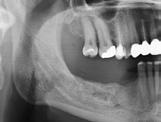

En klassifikation af de tandløse kæber blev i 1988 foreslået af Cawood og Howell (5). Ifølge denne blev den tandløse posteriore mandibel inddelt i seks klasser baseret på graden af atrofi (Fig. 1). Når forholdene og pladsen er væsentligt kompromitterede i forhold til optimal indsættelse af implantater med en passende diameter og længde for den kommende protetiske restaurering, kan kirurgisk forbehandling eller alternative kirurgiske metoder være indicerede. Valget af kirurgisk teknik vil bl.a. afhænge af graden af atrofi. Forskellige behandlingsmodaliteter har tidligere været anvendt til implantatbaseret protetisk rehabilitering af den atrofiske posteriore mandibel,

inklusive indsættelse af korte implantater, sandwich-osteotomi, onlay autolog bloktransplantation, styret knogleregeneration, alveolær distraktions-osteogenese samt transposition eller lateralisering af n. alveolaris inferior (NAI). Imidlertid er den aktuelle afstand fra den øvre begrænsning af canalis mandibulae til toppen af processus alveolaris afgørende for valg af relevant behandlingsmodalitet (6).

Cawood & Howell’s klassifikation af den tandløse posteriore mandibel

Fig. 1. Mandiblen inddelt i seks klasser: Klasse I, betandet posterior mandibel. Klasse II, umiddelbart efter tandudtrækning. Klasse III, velafrundet processus alveolaris med sufficient højde og bredde. Klasse IV, knivskarp processus alveolaris med sufficient højde og utilstrækkelig bredde. Klasse V, flad processus alveolaris med utilstrækkelig højde og bredde. Klasse VI, deprimeret processus alveolaris med varierende grad af basalt knogletab.

Fig. 1. The mandible graduated into six classes: Class I, dentate posterior mandible. Class II, immediately post extraction. Class III, well-rounded ridge form, adequate in height and width. Class IV, knife-edge ridge form, adequate in height and inadequate in width. Class V, flat ridge form, inadequate in height and width. Class VI, depressed ridge form, with some basalar loss evident. III IV VI